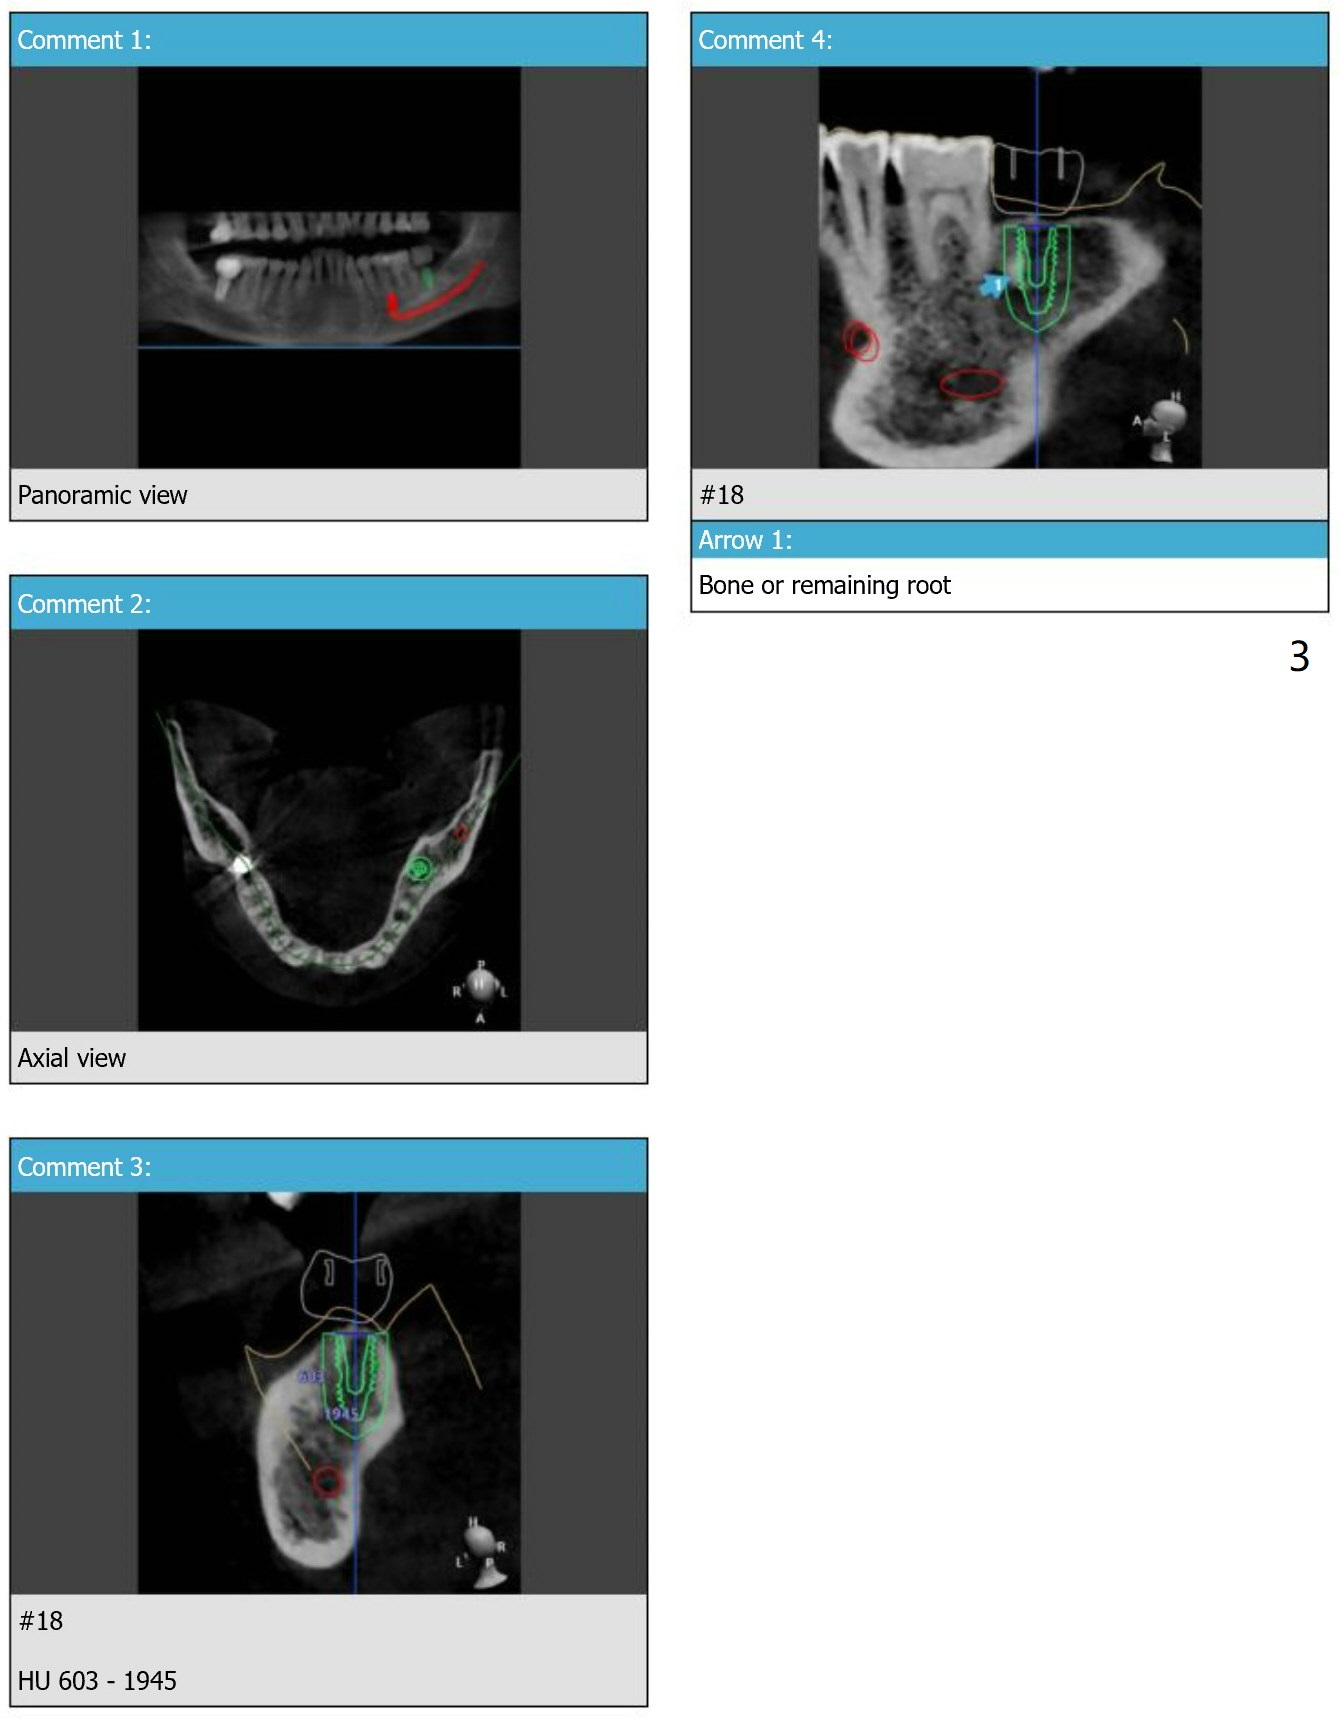

Dense Bone or Residual Root

There is a piece of radiopaque material in the mesial aspect at the site of #18 (Fig.3,4 arrow). After osteotomy and before implant placement, remove the guide to check whether it is dense bone or residual root. Prepare root tip picks. Encourage good oral hygiene (water pik) and postop antibiotic, since he is a diabetic.